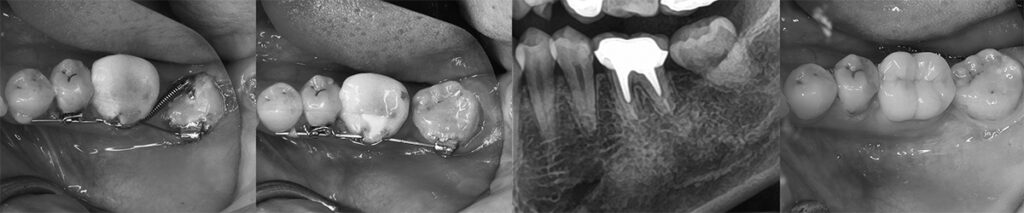

世代が上がれば後方の90度変位した埋伏智歯の移植利用を考えるが歯髄失活は免れないため、困難な矯正であるが萌出間もない大臼歯として今後を託せる生活歯のまま保存する。 矯正用のアンカースクリューと各種装置を智歯に接着させ、移動の各段階で交換しながら抜歯した第二大臼歯部に誘導する。 第一大臼歯は保存治療後ジルコニアセラミック冠で歯冠修復し約7年経過。 治療期間は 2017/12~2019/03

左:治療開始時2017/12 右:健診時2023/07